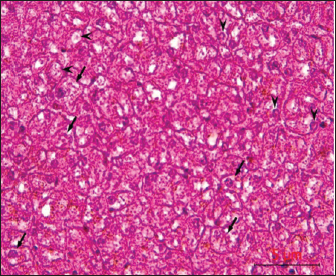

Post-mortem examinations of the dead horses infected with M. haemofelis revealed signs of overall emaciation in the affected animals, paleness of internal organs (Fig. 5), and prominent splenomegaly. The liver, kidneys were enlarged; however, the heart showed white patches. Moreover, histopathological changes were characterized by different histopathological changes of eosinophilic degeneration of cardiac muscle fibers, accompanied by atrophy in some fibers, with bleeding between fibers, besides atrophic glomeruli, accompanied with the dilatation of renal tubules in the kidneys, as well as marked reduction in the proportion of white pulp of splenic tissue and degenerative changes in the cytoplasm of hepatocytes, accompanied by nuclear alterations characterized by loss of chromatin content in the hepatic tissue (Figs. 69).

Fig. 6. Histopathological examination of the heart revealed eosinophilic degeneration (arrows) of cardiac muscle fibers, accompanied by atrophy in some fibers (arrowhead), with bleeding between fibers (asterisk), H&E, 40x.scale bar=5µm.

Fig. 7. Histological section of the kidney showing dilatation of renal tubular lumina (asterisk), with karyopyknosis of the lining epithelial cells (arrows), H&E,40x. Scale bar=5µm.